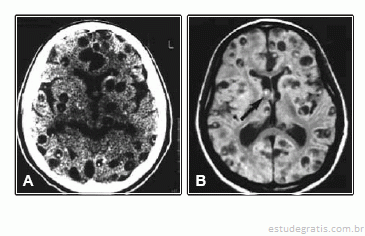

Um homem de 40 anos, imunocompetente, previamente hígido, é atendido no pronto socorro por ter apresentado primeiro episódio de convulsão focal que se generalizou. A tomografia de crânio sem contraste e a ressonância magnética mostram:

O diagnóstico mais provável é de